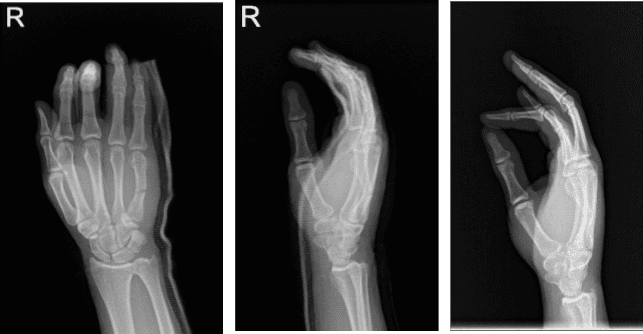

Xray were presented and showed impression as follows: Reidentification of a mildly angulated transverse fracture middle one third right fifth metacarpal. An overlying cast is present.

We tried a closed reduction hematoma block, but this reduction could not be achieved. We discussed treatment options with the patient and the patient opted for surgical management.